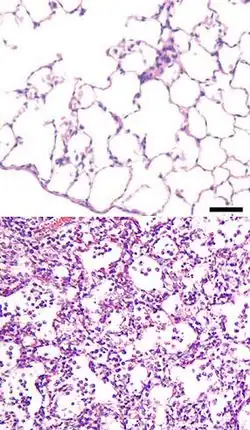

Патогенез пневмонии

Наиболее частым путём проникновения микроорганизмов в лёгочную ткань является бронхогенный — и этому способствуют: аспирация, вдыхание микробов из окружающей среды, переселение патогенной флоры из верхних отделов дыхательной системы (нос, глотка) в нижний, медицинские манипуляции — бронхоскопия, интубация трахеи, искусственная вентиляция лёгких, ингаляция лекарственных веществ из обсеменённых ингаляторов и т. д. Гематогенный путь распространения инфекции (с током крови) встречается реже — при внутриутробном заражении, септических процессах и наркомании со внутривенным введением наркотиков. Лимфогенный путь проникновения встречается очень редко. Далее, при пневмонии любой этиологии, происходит фиксация и размножение инфекционного агента в эпителии респираторных бронхиол — развивается острый бронхит или бронхиолит различного типа — от лёгкого катарального до некротического. Распространение микроорганизмов за пределы респираторных бронхиол вызывает воспаление лёгочной ткани — пневмонию. За счёт нарушения бронхиальной проходимости возникают очаги ателектаза. Рефлекторно, с помощью кашля и чихания, организм пытается восстановить проходимость бронхов, но в результате происходит распространение инфекции на здоровые ткани, и образуются новые очаги пневмонии. Развивается кислородная недостаточность, дыхательная недостаточность, а в тяжёлых случаях и сердечная недостаточность. Больше всего поражаются II, VI, X сегменты правого лёгкого и VI, VIII, IX, X сегменты левого лёгкого. Часто в процесс вовлекаются и регионарные лимфатические узлы — бронхопульмональные, паратрахеальные, бифуркационные.

Крупозная пневмония

Ввиду особенностей развития крупозную пневмонию вполне целесообразно рассматривать как более или менее своеобразную форму пневмонии. При крупозной пневмонии патологический процесс проходит несколько стадий. В I стадии — стадии гиперемии и прилива — воспаление в альвеолах приводит к их расширению и появлению в них экссудата. Во II стадии — стадии опеченения — сначала в альвеолярный экссудат из расширенных сосудов поступают эритроциты. Воздух из альвеол вытесняется. Заполненные фибрином альвеолы придают лёгкому цвет печени. Эта первая часть второй стадии носит название красного опеченения. Далее в экссудате начинают преобладать лейкоциты. Эта часть второй стадии называется серым опеченением. Последняя, III стадия — стадия разрешения: фибрин и лейкоциты в альвеолах рассасываются и частично отхаркиваются с мокротой. I стадия продолжается 2—3 дня, II — 3—5 дней. Разрешение наступает к 7—11-му дню болезни.